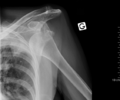

A diagnosis of shoulder dislocation is often suspected based on patient history and physical examination. Radiographs are made to confirm the diagnosis. Most dislocations are apparent on radiographs showing incongruence of the glenohumeral joint. Posterior dislocations may be hard to detect on standard AP radiographs, but are more readily detected on other views. After reduction, radiographs are usually repeated to confirm successful reduction and to detect bony damage. After repeated shoulder dislocations, an MRI scan may be used to assess soft tissue damage. In regards to recurrent dislocations, the supine apprehension test is a useful test in determining athletes who are predisposed to future dislocations.

- An anterior dislocation of the shoulder

Anterior dislocation of the right shoulder. AP X ray

Anterior dislocation of the right shoulder. Y view X ray.